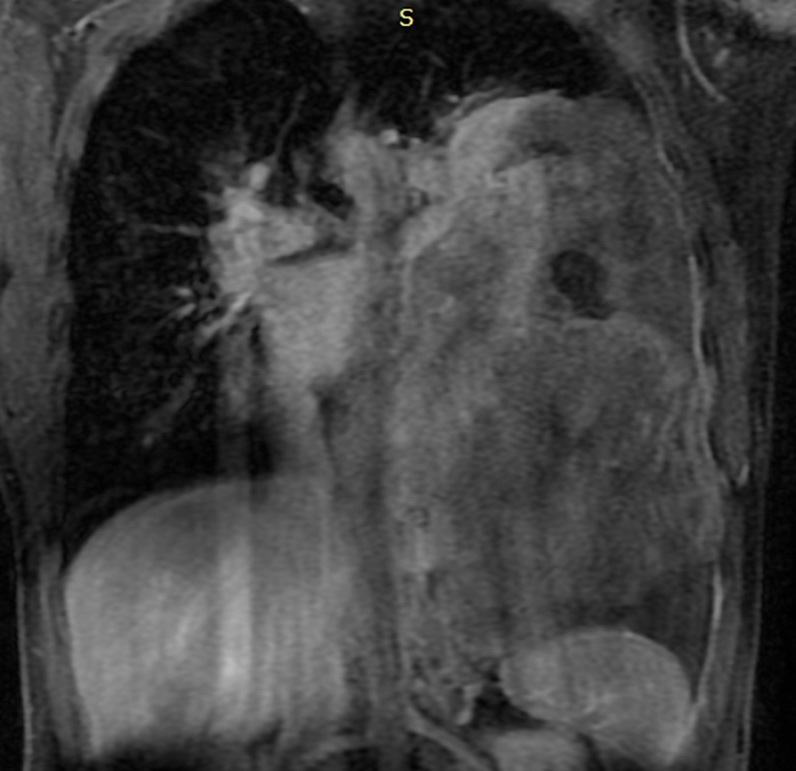

A 28-year-old male patient presented with onset of pain on his left hemithorax and progressive fatigue, in September, 2020. He had no previous comorbidities. An investigative MRI (magnetic resonance imaging) scan showed a large and heterogeneous mass on his left hemithorax with partial lung atelectasis, inferior displacement of diaphragm, mediastinal shift to the right and small pleural effusion (Figures 1a, 1b and 1c). The tumor was in contact with the inferior esophagus and the descending aorta. The thoracic wall (muscle and ribs) was not compromised. These findings suggested, possibly, a mass of pleural origin. An initial core-needle biopsy was performed in October, 2020 to clarify the diagnosis.

Figure 1a: Large solid mass (24 x 10.5 x 14.5 cm) with hemorrhagic areas and heterogeneous post contrast enhancement on the left pleural space.

Figure 1b: The lesion pushes downward the diaphragm, promotes lung atelectasis and displaces mediastinal structures to the right. Minimum pleural effusion is associated (x).

Figure 1c: The mass also and extends to the posterior mediastinal fat (line) close to the descending aorta (star) and esophagus (empty arrow).